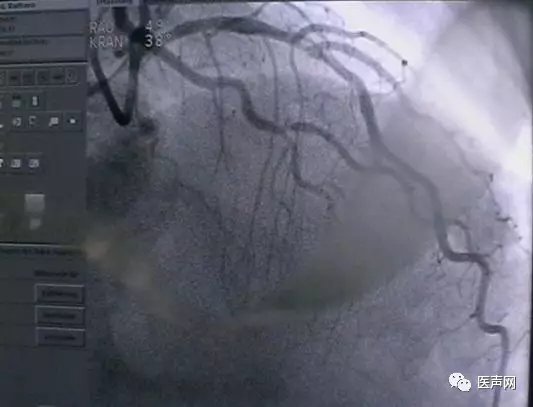

病例4:LAD PCI术后,对角支远端病变

此病变上次PCI不成功,因为LAD有支架,导丝穿过支架网眼入对角支有困难(对角支发出角度很大,成直角(箭头所示)。此次不再尝试,要学会放弃。

见下图: